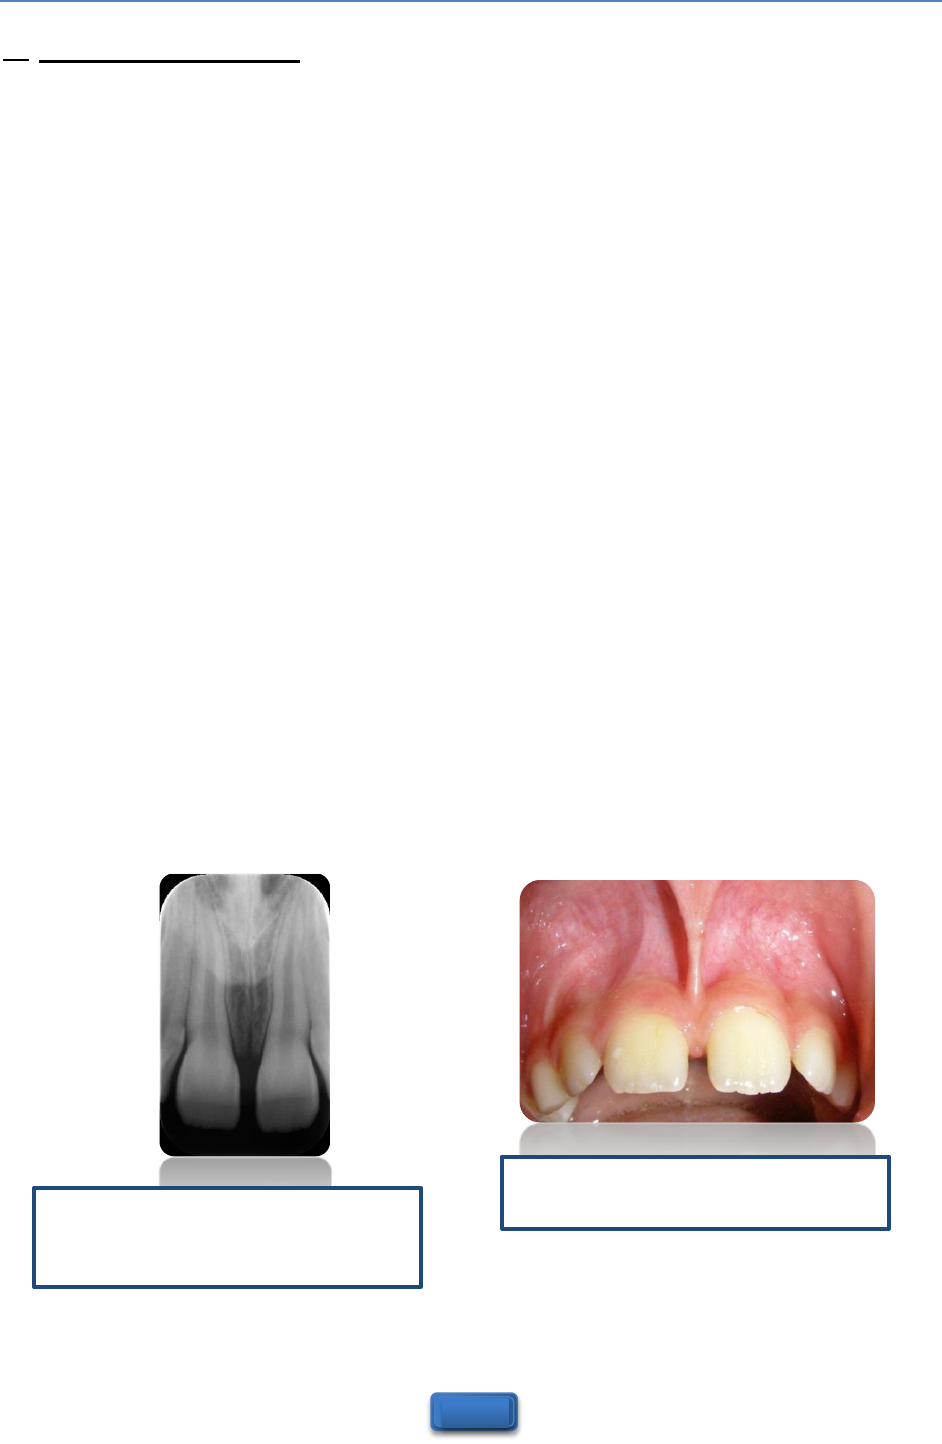

freio labialfreio superiorfreio emfreio bebefreio Freiofreio lingual:freio TUDOfreio ofreio quefreio vocêfreio precisafreio saberfreio sobrefreio ofreio assunto!freio FRENECTOMIAfreio Grátis:freio FREIOS